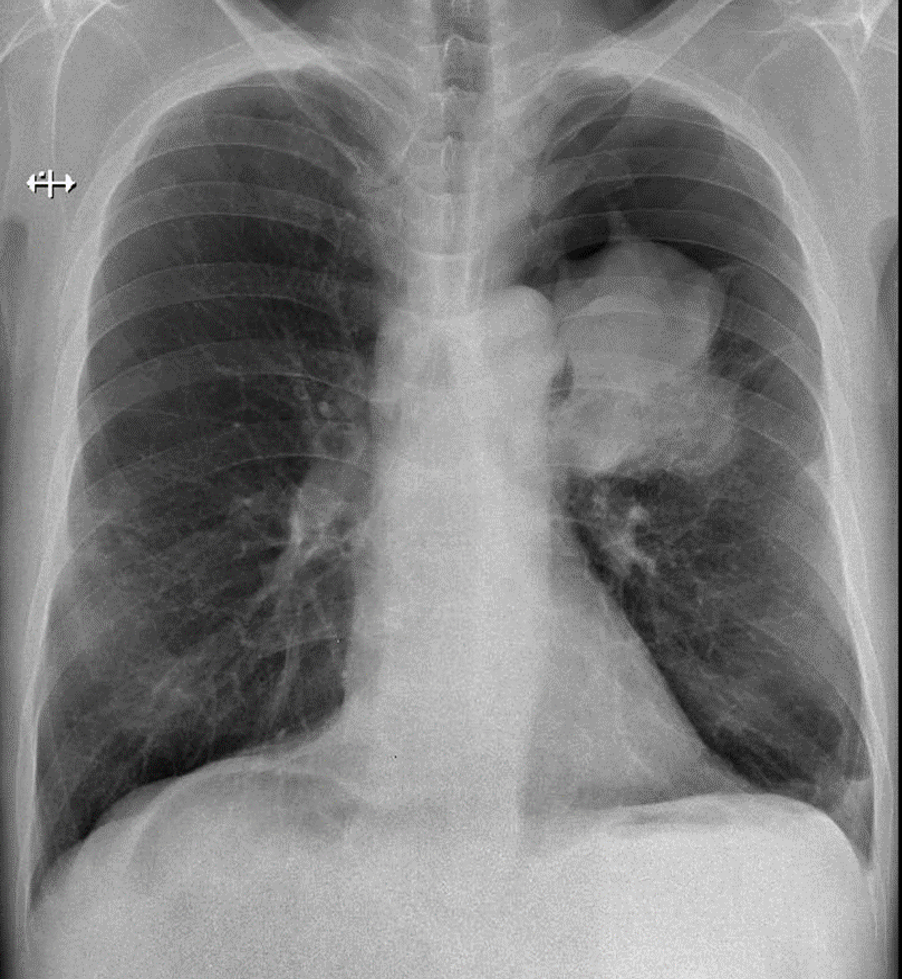

1-U thùy trên phổi (T) vùng cạnh rốn 2-Tràn khí màng phổi (T) vùng đỉnh